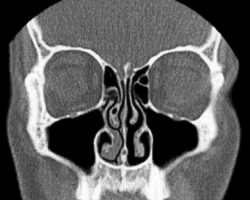

In 1927, Heetderks[4] described the alternating turgescence of the inferior turbinates in 80% of a normal population. According to Heetderks, the cycle is the result of alternating congestion and decongestion of the nasal conchae or turbinates, predominantly the inferior turbinates, which are by far the largest of the turbinates in each nasal fossa. Turbinates consist of bony projections covered by erectile tissue, much like the tissues of the penis and clitoris. The turbinates in one fossa fill up with blood while the opposite turbinates decongest by shunting blood away. This cycle, which is controlled by the autonomic nervous system, has a mean duration of two and a half hours but varies widely with age, body-posture, and other conditions.[5] He further observed and documented that the turbinates in the dependent nasal fossa fill when the patient is lying down. The nasal cycle is an alternation in both time and between left and right sides, with the total resistance in the nose remaining constant. In patients with a fixed septal deviation and intermittent nasal obstruction, the interplay of the nasal cycle becomes evident; the sensation of obstruction frequently mirrors the congestion phase.[6]